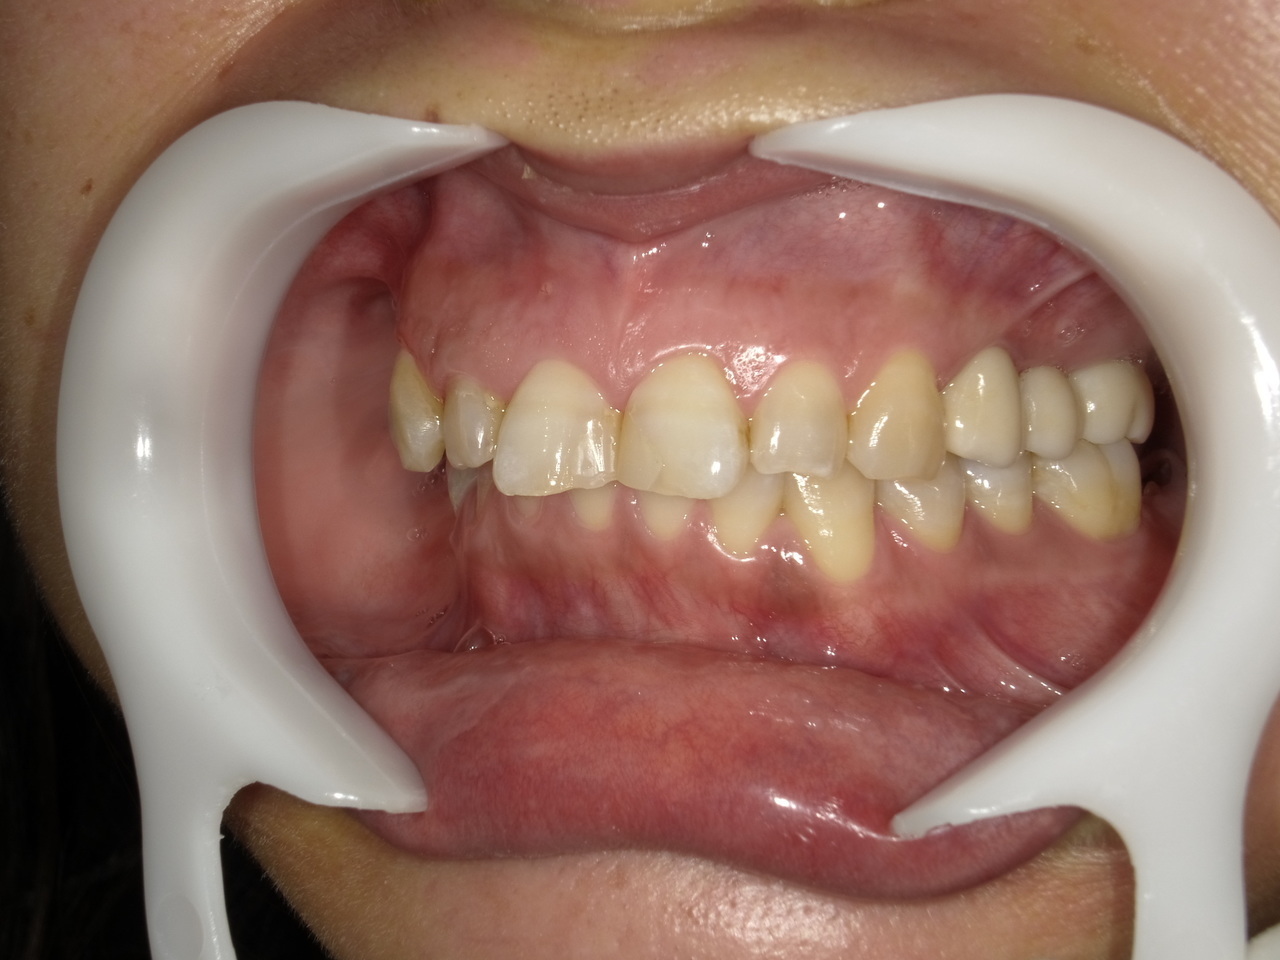

1.左上3番 インプラント抜歯即時埋入即時荷重(手術当日に抜歯を行い、当日に仮歯を入れています。)、左上4番 3ユニット式ブリッジが入るまでの暫間インプラントを埋入して当日に仮歯の装着。 左上5 既存骨3mmのグラフトレスサイナスリフト。最終補綴は、3ユニットジルコニアブリッジで治療を終えた症例

Before

枚方市のインプラントの症例

After

E・S様 女性 60代

患者様の症状としては、左上5番の排膿と重度の歯の動揺、重度の骨吸収、左上3番、中程度の骨吸収と中程度の歯の動揺、自発痛がありました。

治療法としては、左上3456にブリッジ治療が行われていたが、左上5の骨吸収と排膿を認めるために抜歯を行った2か月後に、患者様は、インプラント治療を希望。左上3の骨吸収と動揺も認めていたために、左上3を保存しても将来的な抜歯が予想されたため、左上3抜歯しての左上345の3ユニット式ブリッジ治療の計画を立てインプラント手術を行っています。患者様は、前歯がないことを気にされていたため、左上3番の抜歯と同時の仮歯製作と左上4番暫間インプラントにての仮歯製作を手術と同時に行っています。また、左上3番の歯肉退縮を予防するために、ご自分の歯の一部を温存するルートメンブレンテクニックを行っています。左上5に関しては、既存骨が3mm程度しかないので、グラフトレスサイナスリフトを施行して、表面の骨吸収した部分に骨補填材填入して、ボリュームを維持させていただいています。最終的な3ユニットブリッジは、ジルコニアで製作しています。補綴物の製作に関しては、オールデジタルで行っています。

治療結果は、患者様の希望通り、見えるところの歯がない状態なく、治療を終えることができたことと、また、グラフトレスサイナスリフトを施行することにより、従来のサイナスリフトを施行した場合と比較して、6時か月以上早く治療を終えることができたことと、ルートメンブレンテクニックを行うことで、歯肉退縮を少なくでき、自然な見た目で、最終補綴物を装着できました。従来のGBRやサイナスリフトを行わなかったことにより、短時間で、低侵襲に治療を終えることができ、審美面と機能面の回復を行うことができました。

治療の期間・回数:4か月、10回

治療の価格:814,000円(税込)

治療費の内訳:インプラント基本料(フィックスチャー及び手術費用、投薬費用、レントゲン費用、インプラント上部費用(アバットメントおよびジルコニアクラウンの費用用)右上3番5番 330000円×2 660000円(税込み)オプション費用 右上5グラフトレスサイナスリフト費用 33000円(税込み) 右上3抜歯即時荷重費用 33000円(税込み) 暫間インプラント費用 0円

治療のリスクや副作用:手術後に、痛みや腫れ、出血、合併症などを引き起こす可能性があります。噛む感覚がご自身の歯と異なる場合があります。見た目がご自身の歯と異なる場合があります。手術後にメインテナンスを継続しないと、インプラントが抜け落ちる可能性があります。